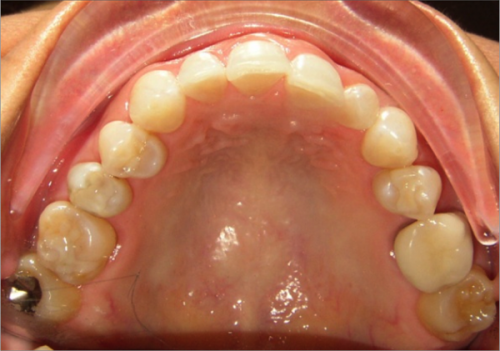

45 year old female:

Diagnosis:

- Missing upper left second bicuspid

- Lower arch crowding

- Edge to edge bite

Treatment:

- Extraction of upper & lower right second bicuspids

- Full fixed appliances

- 21 months